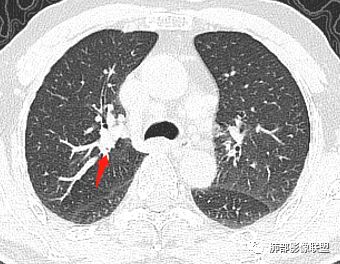

老年男性,亚急性病程,咳嗽咳痰。右肺中叶团片影,外朝内分布,大部分边界清楚平直,内侧支气管进入,团片影见低密度坏死区,强化明显,延迟强化,血管破坏不明显,符合爬行征5个特点:

1.肺外周生长。

2.外侧部分体积大于内侧。

3.病变最大径与肺的纵轴及水平面任何一条轴线不平行。

4.病变内侧支气管通畅。

5.病变区域肺容积无缩小。

双侧肺门及纵隔淋巴肿大并可见钙化。考虑结核,但部分边缘膨隆,肿瘤待排。

主病灶在中叶,但是左肺舌段叶有条索影,陈旧病变。蓝色箭头支气管受压,是淋巴结肿大

主病灶在中叶,但是还有结节状病变在下叶

这个支气管是走形通畅,但是壁增厚的。比较符合炎症改变

内侧段是通畅但是受压的

外侧段一开始狭窄

但是远端通畅,所以我认为支气管都没有堵塞,不太可能是鳞癌

边缘还有多发小灶

淋巴结肿大,钙化。

病灶明显平直,中央是粘液栓,低密度,分界清楚

吴婧老师和南边老师都对该病例进行了深入分析。从支气管管壁的增厚,支气管狭窄后扩张,支气管粘液栓,病灶形态,到病灶不均匀强化及坏死彻底,到周边病灶及肺组织空气的潴留,加之纵隔内淋巴结肿大伴钙化等等,都支持慢性炎性病灶,尤其是结核。

墨西哥仙人掌征---结核        影像上结核灶,粗大的均匀枝干,推测是支气管囊状扩张引起的,在非支气管区,形成圆形坏死囊群;如果这些坏死比较稀薄,又遇到扩张支气管,就会形成粗大的“墨西哥仙人掌”。结核引起的支气管近端炎症纤维化,可以造成支气管阻塞,从而将干酪样坏死物封堵在管腔内。仙人掌主干内部应该是干酪为主,稀薄的,具有流动性,时间久了会出现钙化。